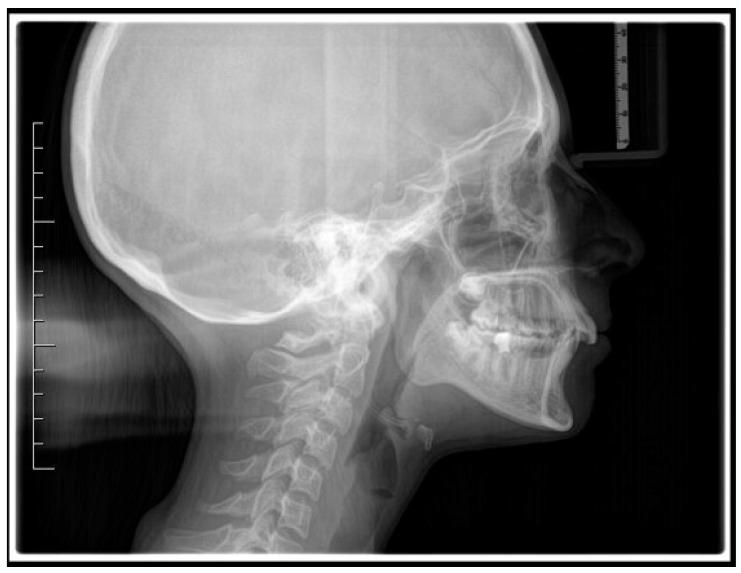

Successful closure of edentulous spaces with clear aligners (CAs) is influenced by many factors. CAs are tailored orthodontic devices whose predictability may have relevant medico-legal implications. This study presents a scoping review about missing molar space closure (MMSC) with CAs and a clinical case. This study aims to highlight the feasibility of molar space closure by mesialization with CAs without hybrid supports. Following PRISMA Sc-review guidelines, English-written randomized/non-randomized/observational clinical studies on PubMed, Scopus, Cochrane and Lilacs were searched. An 18-year-old patient, with upper and lower edentulous spaces due to the loss of two first molars, was rehabilitated with CAs (Sorridi, Sorridi srl, Latina, Italy) without hybrid supports and attachments. The therapy was carried out over 10 months. Currently, there are no studies documenting MMSC by mesialization with only CAs. Existing articles document the closure of premolar or incisor spaces. The upper and lower left second molars replaced the missing first molars, and erupting third molars replaced adjacent teeth. The biomechanical effects in space closure with CAs related to extraction cases appear as priorities of clinical/medico-legal interest. Our case turns attention to this movement of CAs without attachments/hybrid supports, indicating that even such a complex treatment can be comfortable for patients and safely predictable for specialists.

使用透明矫治器(CA)成功关闭无牙间隙受多种因素影响。CA是定制的正畸装置,其可预测性可能具有相关的医疗法律意义。本研究呈现了一项关于使用CA关闭缺失磨牙间隙(MMSC)的范围综述及一个临床病例。本研究旨在强调在无混合支持的情况下通过CA近中移动关闭磨牙间隙的可行性。遵循PRISMA范围综述指南,检索了PubMed、Scopus、Cochrane和Lilacs上英文撰写的随机/非随机/观察性临床研究。一名18岁患者因两颗第一磨牙缺失导致上下无牙间隙,使用CA(Sorridi,Sorridi srl,拉蒂纳,意大利)进行修复,无混合支持和附件。治疗持续了10个月。目前,尚无研究记录仅通过CA近中移动关闭MMSC的情况。现有文章记录了前磨牙或切牙间隙的关闭。上下颌左侧第二磨牙替代了缺失的第一磨牙,萌出的第三磨牙替代了相邻牙齿。与拔牙病例相关的CA关闭间隙的生物力学效应似乎是临床/医疗法律关注的重点。我们的病例将注意力转向了无附件/混合支持的CA这种移动方式,表明即使是如此复杂的治疗对患者来说也可以是舒适的,对专家来说也可以是安全可预测的。